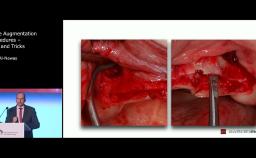

Surgical Planning and Procedures

Peri-Implant Soft-Tissue Management and Integration

One of the greatest challenges facing clinicians is to obtain an early and long-standing effective mucosa seal, capable of biologically protecting the peri-implant structures. This is particularly difficult in compromised sites, due to trauma, atrophy, and/or periodontal disease. Recent systematic reviews have confirmed that the presence of an appropriate amount of keratinized mucosa is desirable.